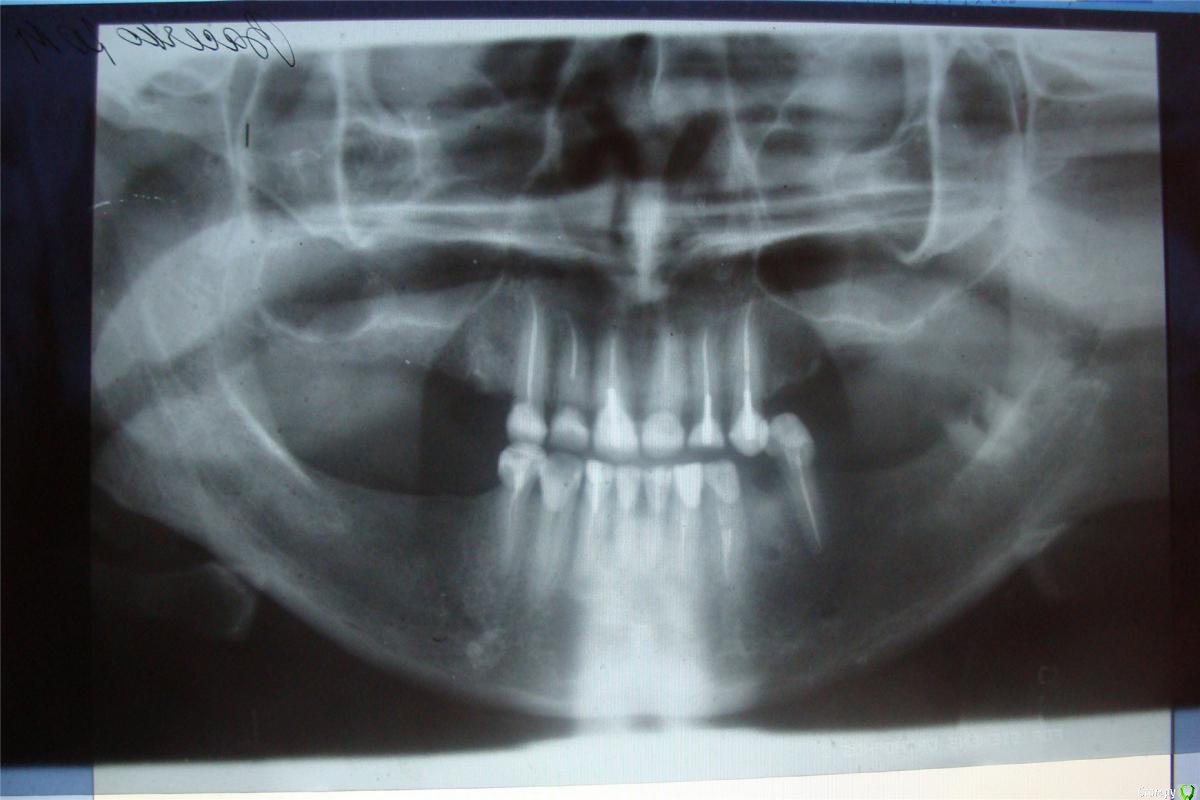

jell273 Опубликовано 12 июля, 2016 Поделиться Опубликовано 12 июля, 2016 Всем доброй ночи. В прошлой теме http://forum.stom.ru/topic/10643-ochen-slozhnoe-protezirovanie-pomogite/, я писала о плане протезирования и установки имплантов. Все манипуляции с зубами , были закончены в 2011 году и радостно ходила до ноября 2015 года. Пока верхние, левые импланты не стали качаться и не выпали,, Потом оказалось, что у меня Гаймороэтмоидит. Болей особо не было и доктор , мне через разрез в десне, пытался, почистить гайморову пазуху. Толку было ноль,. Потом был 1 мед. Проколы, уколы, таблетки и.т д. Вроде все вылечили. Хотя до имплантации , гайморитов не было. Сейчас сделали сьемный протез, . К осени, доктор хочет нарастить кость , с синуслифтингом. Подождать месяцев 6???.. Потом поставит импланты, и только потом через еще несколько месяцев коронки. Гарантии, что, что то пойдет не так никто не дает. Не лор, не имплантолог. Врач у меня, очень хороший и грамотный. У меня, к вам вопрос, уважаемые врачи. Были ли случаи, выпадения имплантов, через 4 года??? Или , мне одной, так не повезло??? Шок уже прошел. Теперь с врачем , пытаемся действовать очень осторожно. Остальные импланты стоят на месте и слава богу не шатаются. Снимки прилагаю. Спасибо Ссылка на комментарий

jell273 Опубликовано 13 июля, 2016 Автор Поделиться Опубликовано 13 июля, 2016 у живых людей и не такое бывает.Можете показать более ранний снимки? Есть снимок без имплантов. red_butler, странно просто. Стояли себе импланты, как влитые и потом через 4 года стали шататься, да так, что доктор их вытащил руками. Можно предположить, что все это время, был хронический гайморит, который я не замечала и кость постепенно стала уходить. Но как можно, не заметить Гайморит ??.Диабета нет . Есть гастрит, холецистит и аденомиоз. Но как, эти заболевания, влияют на убыль кости.??? Ссылка на комментарий